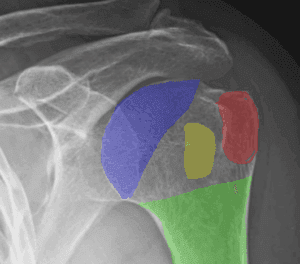

Diagnosing Proximal Humerus Fractures:

- Imaging:

- X-rays: Standard views to assess the fracture.

- CT Scans: Detailed images for complex fractures.

Types of Fractures:

- Neer Classification: Based on the number of fracture parts and their displacement.

- AO Classification: Detailed classification considering the fracture pattern.